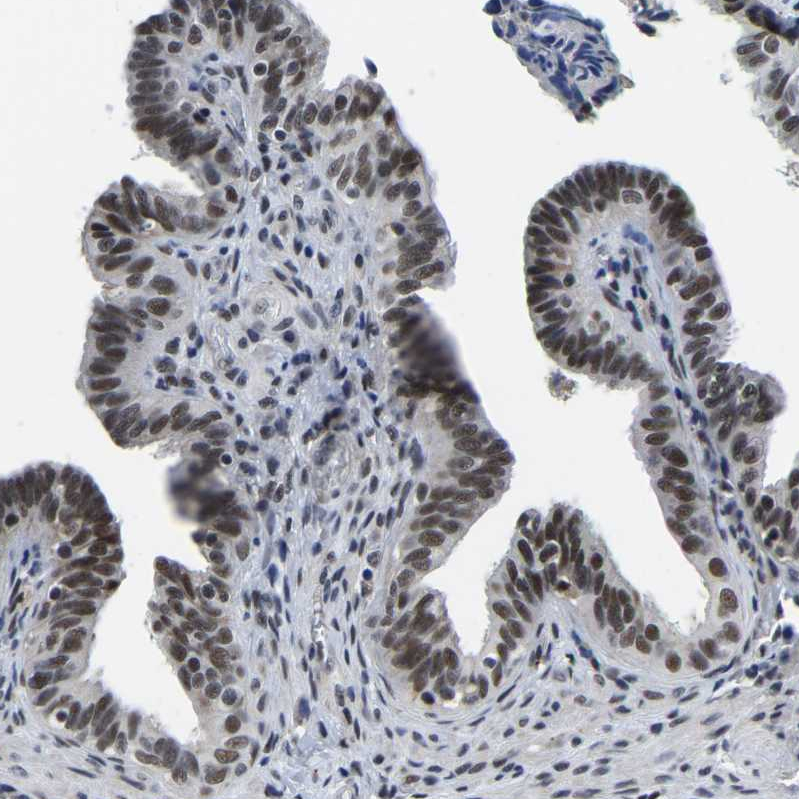

Immunohistochemical staining of human testis shows strong nuclear positivity in cells in seminiferous ducts.